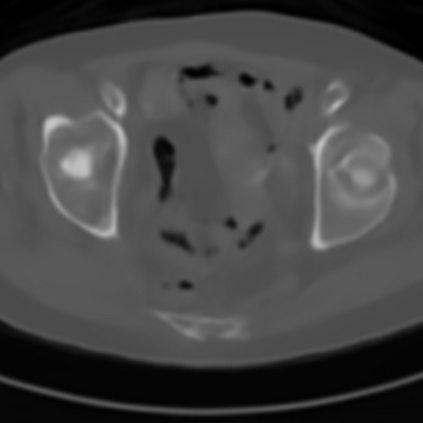

Sparse-view computed tomography (CT) -- using a small number of projections for tomographic reconstruction -- enables much lower radiation dose to patients and accelerated data acquisition. The reconstructed images, however, suffer from strong artifacts, greatly limiting their diagnostic value. Current trends for sparse-view CT turn to the raw data for better information recovery. The resultant dual-domain methods, nonetheless, suffer from secondary artifacts, especially in ultra-sparse view scenarios, and their generalization to other scanners/protocols is greatly limited. A crucial question arises: have the image post-processing methods reached the limit? Our answer is not yet. In this paper, we stick to image post-processing methods due to great flexibility and propose global representation (GloRe) distillation framework for sparse-view CT, termed GloReDi. First, we propose to learn GloRe with Fourier convolution, so each element in GloRe has an image-wide receptive field. Second, unlike methods that only use the full-view images for supervision, we propose to distill GloRe from intermediate-view reconstructed images that are readily available but not explored in previous literature. The success of GloRe distillation is attributed to two key components: representation directional distillation to align the GloRe directions, and band-pass-specific contrastive distillation to gain clinically important details. Extensive experiments demonstrate the superiority of the proposed GloReDi over the state-of-the-art methods, including dual-domain ones. The source code is available at https://github.com/longzilicart/GloReDi.